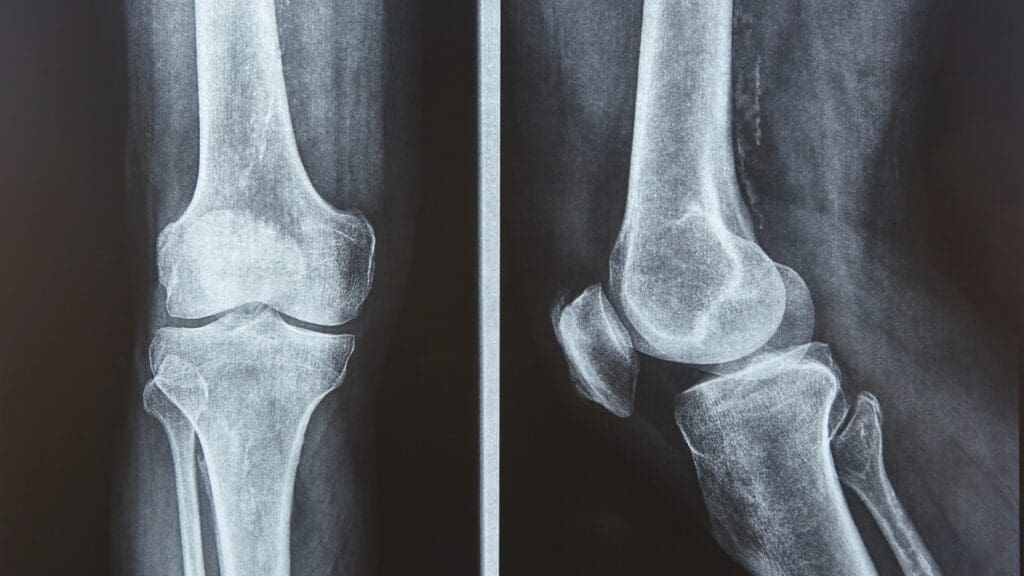

Imaging helps confirm Osgood Schlatter disease, though it’s not always needed. X-rays show signs like tibial tubercle irregularities, swelling, and sometimes an elevated tubercle.

Diagnosis involves a medical history, physical exam, and imaging studies like X-rays. These help rule out other conditions.